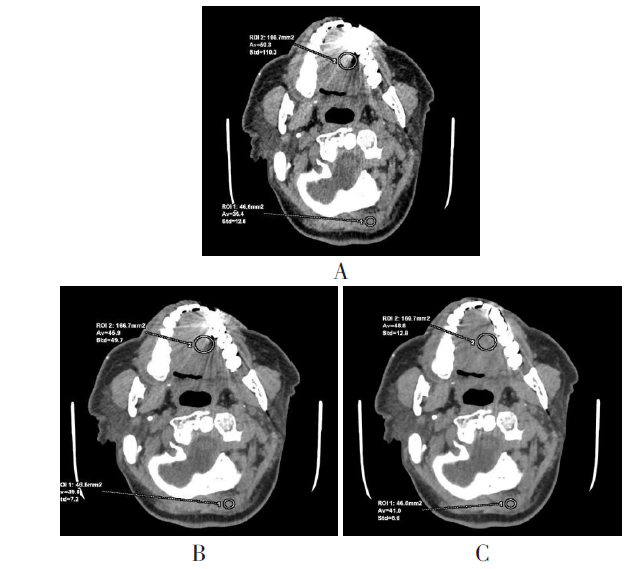

图1 ROI的选择示意图 A:QC图像,义齿周边高密度硬化伪影及小片低密度暗区;B:单能谱110 keV+MARs图像,义齿周边无明显金属伪影,邻近软组织成像清晰;ROI1:同层面后颈部头夹肌的CT值、SD值;ROI2:受义齿干扰的口腔中舌部软组织明暗相间伪影区的CT值、SD值;窗宽300 HU、窗位35 HU。

Fig.1 Schematic diagram of ROI selection